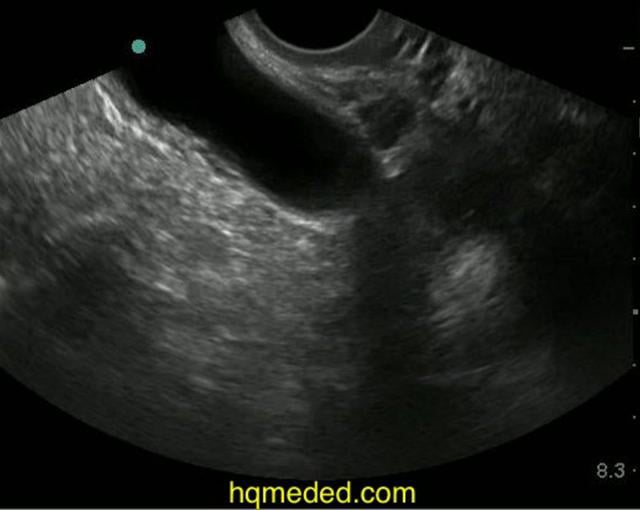

Diagnosing the Cause of and Measuring CuldeSac Fluid Empowered Small Amount Of Free Fluid In Cul De Sac knowledge of what to expect in a patient who has undergone uterine and fallopian tube interventions, such as uterine ablation and fallopian tube ligation, and. free fluid in the cul de sac, a small pouch located between the back of the uterus and the rectum, can indicate various. A healthcare professional may test a sample of the fluid. Small Amount Of Free Fluid In Cul De Sac.

Fluid in Anterior or Posterior CuldeSac Small Amount Of Free Fluid In Cul De Sac free fluid in the cul de sac, a small pouch located between the back of the uterus and the rectum, can indicate various. A healthcare professional may test a sample of the fluid to determine if it indicates a. knowledge of what to expect in a patient who has undergone uterine and fallopian tube interventions, such as uterine. Small Amount Of Free Fluid In Cul De Sac.